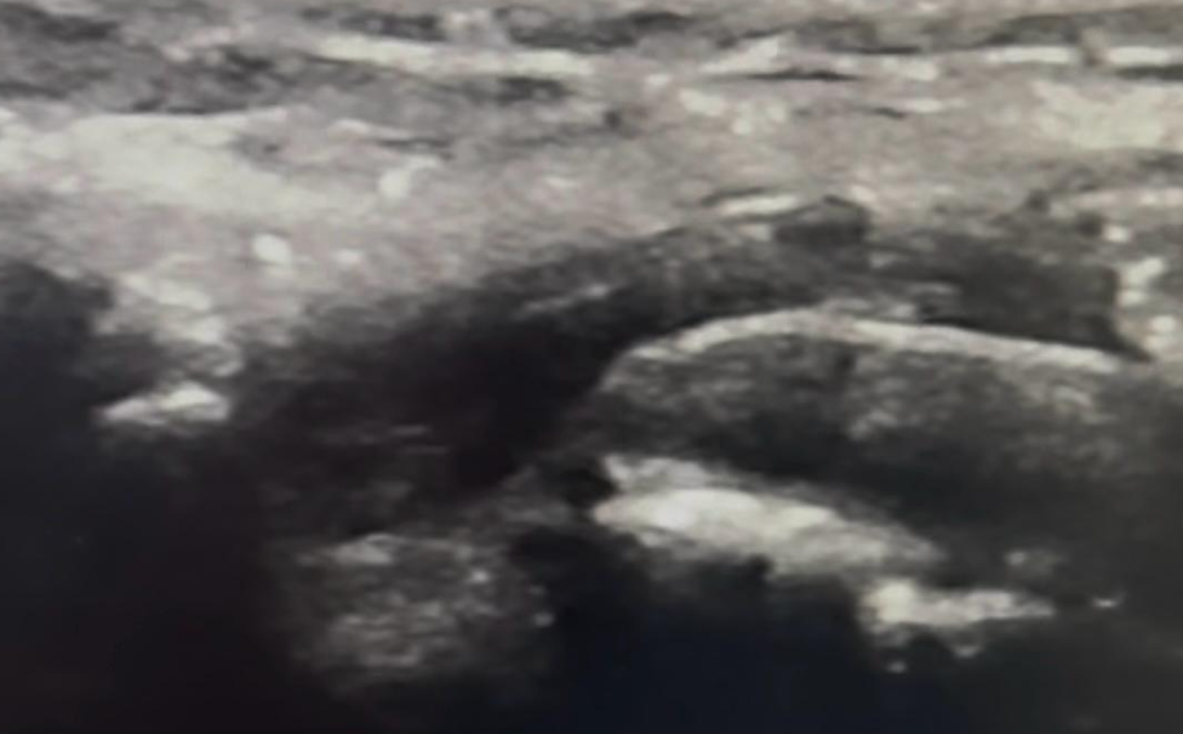

Pylephlebitis with Bacteremia from a Rare Bacterium: A Case Report of Septic Mesenteric-Portal Thrombophlebitis Associated with Acute Diverticulitis

Paula Heroso Moreira, Giovana Rezende Fernandes Costa Costa, Lucas Terasoto, Gabriel da Silva Eli, Barbara Loeser Faro, Pedro Henrique Garcia Parreira, Pedro Henrique Garcia Parreira, Adonis Nasr